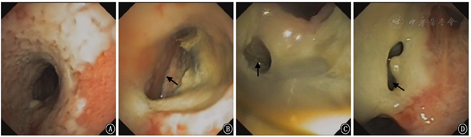

2018年5月23日复查胸部CT提示:淋巴瘤治疗后,气管瘘、纵隔瘘;纵隔、右侧锁骨上窝多发肿大淋巴结,双肺多发结节,脾脏占位,符合淋巴瘤,部分较前减小;双肺感染较前加重,双肺下叶膨胀不全;新增双侧胸腔积液;心包少量积液,较前相仿(图2)。2018月5月25日支气管镜见气道内弥漫白斑、黏膜糜烂,气管中段见巨型气管-纵隔瘘,左主支气管见3个瘘口,右上叶见1个瘘口(图3)。患者治疗过程中新发气管、支气管-纵隔瘘,考虑为原淋巴瘤浸润,累及纵隔及邻近的气管、支气管;化疗后,肿瘤组织消减,导致气管、支气管与纵隔间出现相通的窦道。患者气道弥漫性糜烂、多发巨型瘘口,难以自行愈合。目前气道内介入治疗方法,如气道支架、封堵器等不能解决瘘口问题,且支架、封堵器等机械压迫可能使原有气管/支气管瘘扩大。考虑患者气管/支气管-纵隔瘘虽存在,但纵隔内气体尚未引起心脏和纵隔大血管压迫;且瘘口未与食道相通,未引起难治性肺部感染等危及生命情况,决定采取保守治疗方式,继续予抗感染(产气肠杆菌和放线菌)及对症支持治疗。患者症状好转于2018年6月5日出院。但患者因个人因素,放弃进一步治疗,并于出院后2个月去世。

注:箭头示瘘口位置